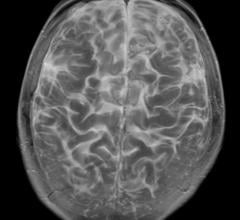

October 18, 2017 — Magnetic resonance imaging (MRI)-based measurements of the functional connections in the brain can ...